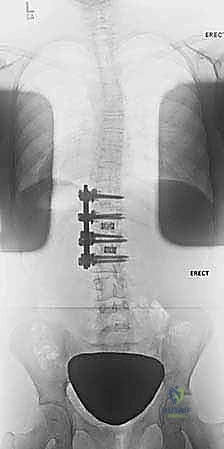

2. التصوير بالأشعة السينية (X-Rays)

هو المعيار الذهبي لتشخيص الجنف. يتم التقاط صور شعاعية لكامل العمود الفقري (من الرقبة إلى الحوض) من الأمام والخلف والجانب، والمريض في وضع الوقوف. من خلال هذه الصور، يقوم الدكتور هطيف بـ:

* قياس زاوية كوب (Cobb Angle): وهي الزاوية التي تحدد شدة الانحناء. الانحناءات الأكبر من 10 درجات تُعتبر جنفاً.

* تقييم النضج العظمي (Risser Sign): من خلال فحص عظام الحوض لمعرفة ما إذا كان المريض لا يزال ينمو، مما يساعد في التنبؤ باحتمالية تدهور الانحناء.